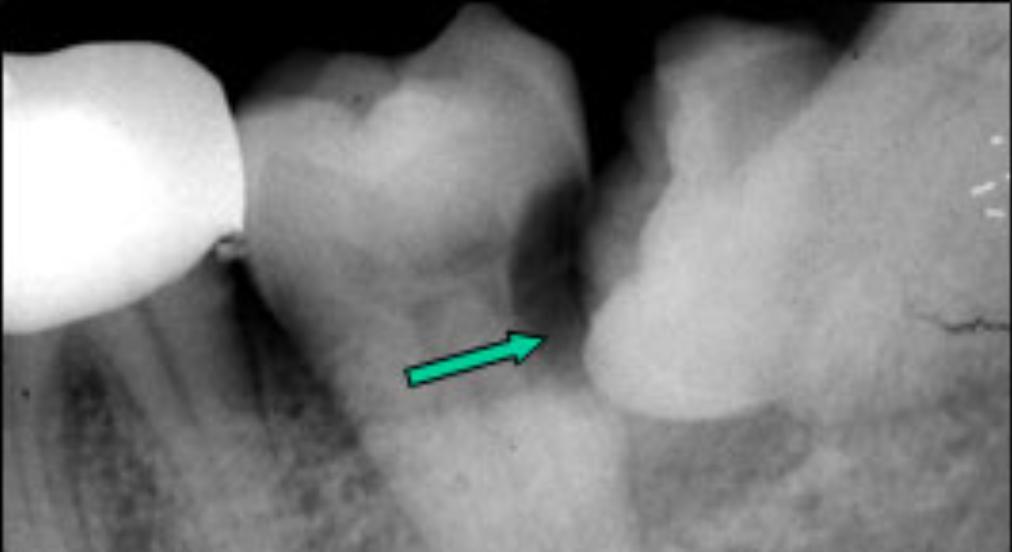

2)龋坏:

由于智齿本身生长位置就比较靠后,清洁起来有一定难度,所以蛀牙情况很普遍,有些智齿不甘寂寞自己蛀牙,还会把前牙累及。

3)塞牙:

很多时候智齿的生长会和前牙形成一个夹角,形成一个空间。食物往往会嵌塞其中,让您感到不适。长期的食物嵌塞不光会造成牙龈的红肿、退缩,甚至可以是牙槽骨吸收,形成恶性循环,加重食物嵌塞。

4)根、骨吸收:

由于智齿生长持续的压力压迫,造成邻近牙齿、骨质的吸收。可导致邻牙不适、疼痛甚至松动脱落。